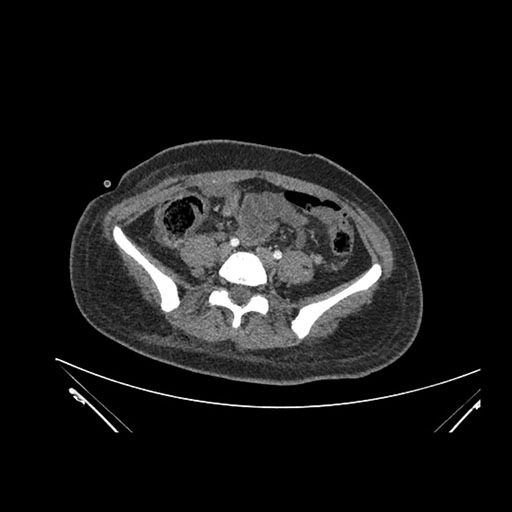

Imaging Analysis

Look through the patient's CT scan to identify any areas of concern for the necessary procedure.

Axial Venous

Based on initial findings, which issue(s) would you be most concerned about?